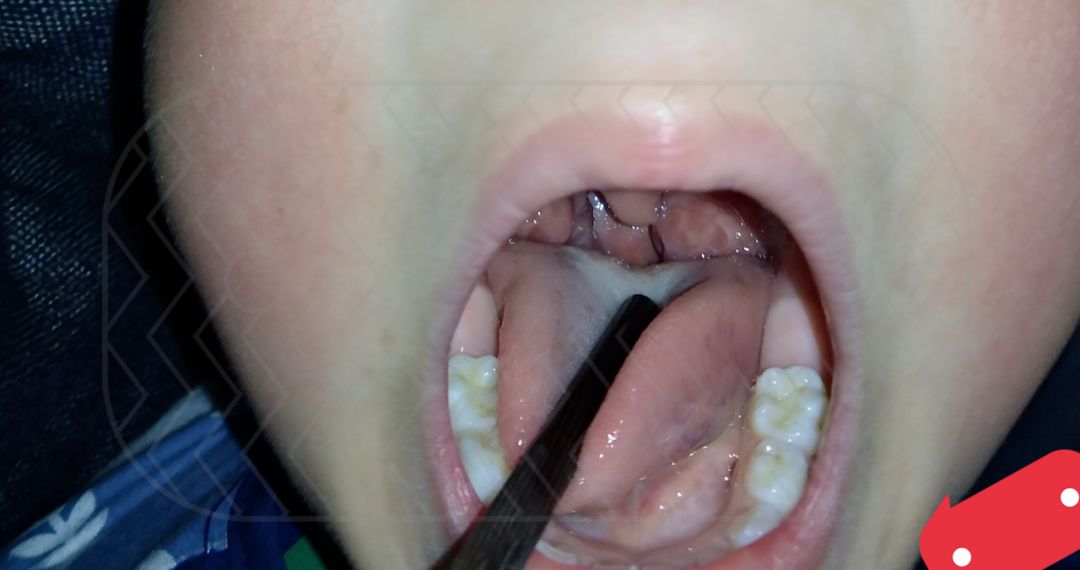

(图片来源:爱儿康家长提供)「扁桃体」位于消化道和呼吸道的交汇处,是咽淋巴循环的一部分,有一定的免疫功能。可是,要是它发炎了,不仅遭罪的是孩子,还会引发嗓子痛、发烧、淋巴结肿大等一系列的不适症状。不过,不是说「扁桃体经常发炎」就等于「可以切除」。毕竟“扁桃体”发炎连累心脏和肾,一旦治疗方式有误,可能会得不偿失。所以,做任何决定前都要慎重。至于「宝宝扁桃体为啥总是发炎?」、「抗生素可以治疗扁桃体炎症吗?」以及「扁桃体该不该切?」今天小康君就给大家好好讲讲扁桃体这厮~

(图片来源:爱儿康家长提供)扁桃体炎可分为急性扁桃体炎和慢性扁桃体炎。

但是最为典型的表现还是扁桃体充血、红肿,部分患儿的扁桃体表面可见到黄白色的脓点,或在扁桃体表面有黄白色的豆渣样渗出物。

(图片来源:爱儿康家长提供)

虽然扁桃体是免疫系统的第一道防线,但当扁桃体“病了”就会失去它原本的防御功能。

情况严重时,发炎的扁桃体被迫变成“叛军”,成为致病菌的庇护所。